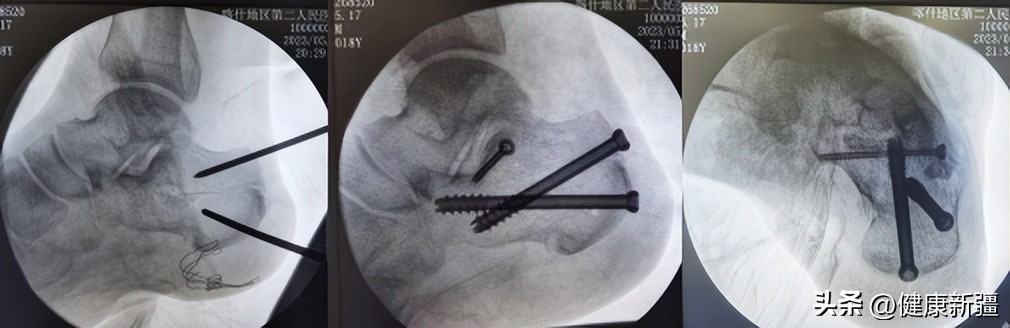

手术中

术前,上海援疆专家、喀什二院骨科主任王建广带领骨科副主任项飞及骨科医护团队,结合患者CT等影像学检查及查体结果,制定了详细手术方案。手术采取了微创新疗法——跟骨粉碎性骨折经皮微创空心螺钉内固定术,即通过几个不到“1厘米”微创切口精细完成骨折的复位和固定。术中几乎没有出血,术后第二天即可开展康复训练,患者非常满意。

此项技术具有创伤小、切口并发症少等优势,避免了常规切口皮肤容易坏死和感染的并发症,只要患者全身条件允许,手术可于伤后即刻或3-5天内进行,但对医生综合能力要求较高,需具备丰富的救治经验和娴熟的手术技巧。